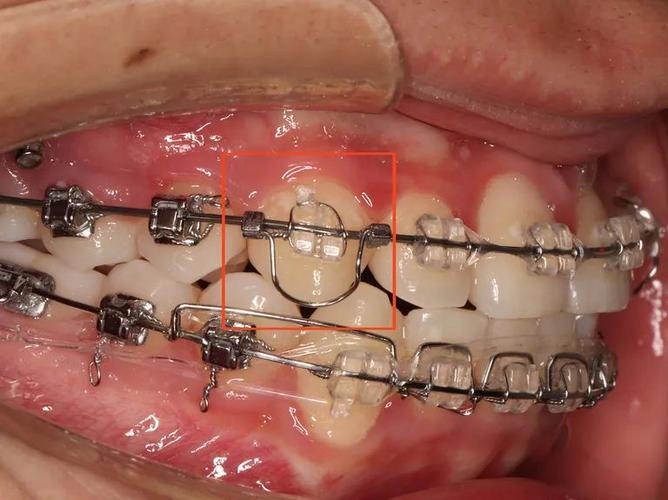

安装与结扎

将弯制好的辅弓纳入托槽(通常使用0.022英寸或0.018英寸托槽系统),通过结扎丝或橡皮圈固定于目标牙位,安装时需检查弓丝是否完全入槽,避免因结扎过紧导致力量过大,或过松导致力量不足,对于需配合支抗的病例(如种植钉),需先将辅弓与支抗装置连接,再结扎至目标牙齿。